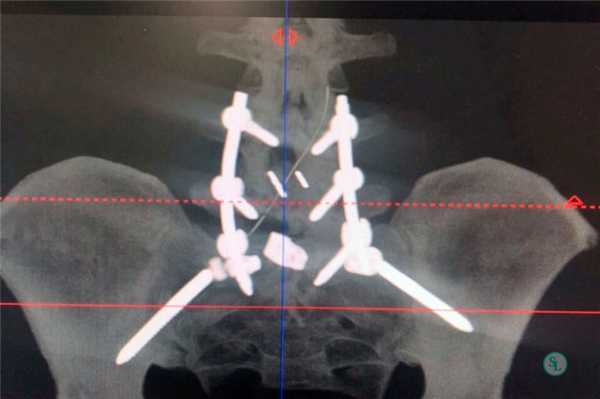

Когда удаляют полностью диск, нередко в освобожденную межпозвонковую полость помещают имплантат, скрепив позвонковую пару стабилизирующей системой. В позвоночник вставлены титановые болты для прочной фиксации поперечного стабилизатора, который в свою очередь будет отвечать за правильное положение относительно хребтовой оси смежных костных тел. Вкручивание болтов осуществляется через дужку в тела позвонков. Современная металлоконструкция обычно представлена динамическими болтами, что позволяет сохранить подвижность прооперированного уровня, максимально приближенную к норме.

Пример такой операции на рентгене.